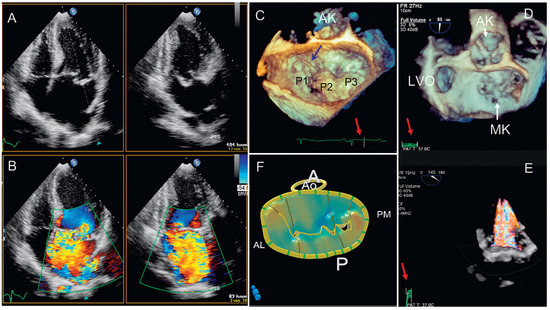

Dreidimensionale Echokardiographie zur Beurteilung der Mitralklappe

by Patric Biaggi, Christian Felix, Matthias Greutmann, David Hürlimann, Dominique Bettex and Felix C. Tanner

Using two-dimensional echocardiography, the complex anatomy of the mitral valve needs mental reconstruction into its three-dimensional shape. The power of both transthoracic and transesophageal three-dimensional echocardiography (3DE) lies in its possibility of showing the complex mitral valve anatomy in one single image, as [...] Read more.

Using two-dimensional echocardiography, the complex anatomy of the mitral valve needs mental reconstruction into its three-dimensional shape. The power of both transthoracic and transesophageal three-dimensional echocardiography (3DE) lies in its possibility of showing the complex mitral valve anatomy in one single image, as opposed to the mental reconstruction based on multiple two-dimensional images and schematic assumptions. Several 3DE modalities are used in daily life, including real time (“live”) modes as wells as postprocessed images. 3DE is of special interest in the evaluation of mitral stenosis, complex mitral valve prolapse and mitral valve prostheses. It has an established role in the perioperative mitral valve assessment during mitral valve surgery as well as during percutaneous mitral valve procedures. Limitations of 3DE are relatively low frame rates, an important learning curve as well as timeconsuming processing. Full article

Show Figures

Figure 1